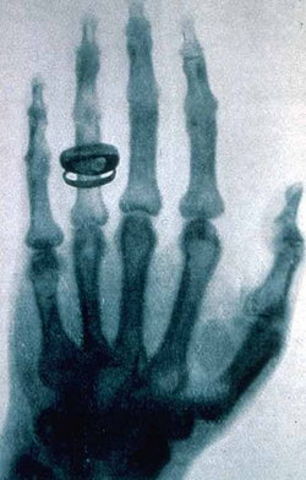

• Rayos X

Rayos X

La denominación rayos X designa a una radiación electromagnética, invisible, capaz de atravesar cuerpos opacos y de imprimir las películas fotográficas. Los actuales sistemas digitales permiten la obtención y visualización de la imagen radiográfica directamente en una computadora (ordenador) sin necesidad de imprimirla. La longitud de onda está entre 10 a 0,01 nanómetros, correspondiendo a frecuencias en el rango de 30 a 3000 PHz (de 50 a 5000 veces la frecuencia de la luz visible).